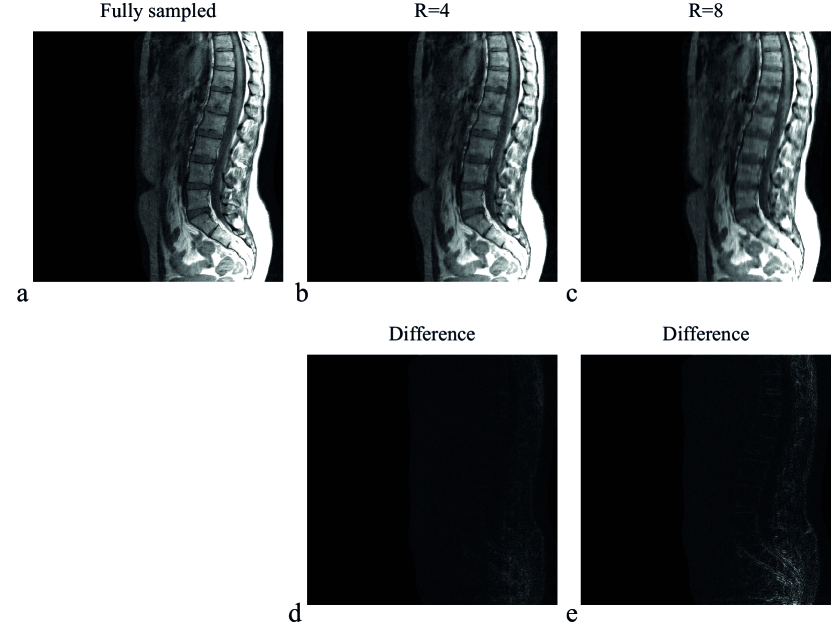

Figure 3 shows the T1-weighted TSE spine images for a reconstruction matrix size of , reconstructed with the SB implementation for a fully sampled data set and for undersampling factors of four (R=4) and eight (R=8), where Cartesian sampling masks were used. The quality of the reconstructed images for R=4 and R=8 demonstrate the performance of the compressed sensing algorithm. The difference between the fully sampled and undersampled reconstructed images are shown in Fig. 3d and Fig. 3e for R=4 and R=8, respectively.